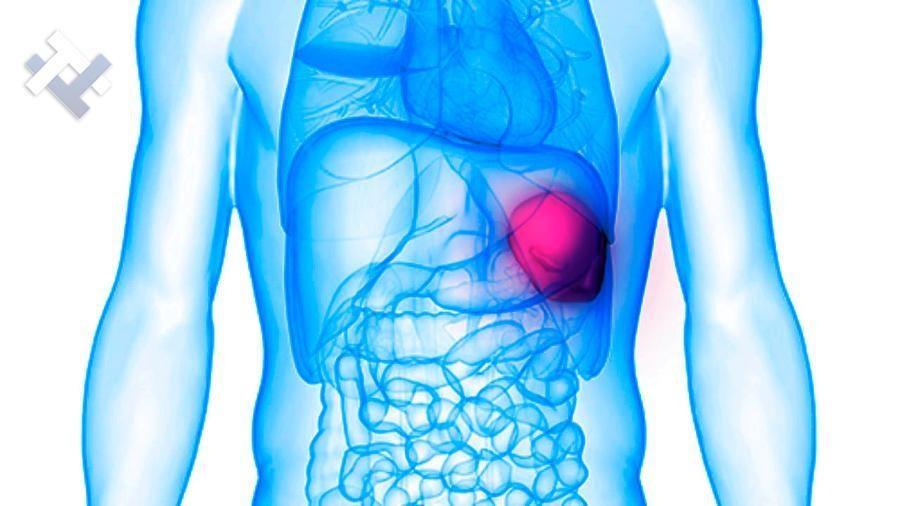

Ο Γενικός Χειρουργός Λιάγκος Γεώργιος MD PhD εκτελεί τις επεμβάσεις Λαπαροσκοπικά, Ενδοσκοπικά, Ανοιχτά Ελάχιστα Επεμβατικά και με Laser. Η θεραπεία εξατομικεύεται σε κάθε ασθενή ανάλογα με τις ανάγκες του. Αναλαμβάνει περιπτώσεις όπως κήλες και κοιλιοκήλες (αντιμετώπιση βουβωνοκήλης, αντιμετώπιση ομφαλοκήλης, θεραπεία επιγαστρικής κήλης, κήλη των αθλητών (Σύνδρομο κοιλιακών προσαγωγών), αντιμετώπιση μετεγχειρητικής κήλης, θεραπεία Μηροκήλης), πέτρες στη χοληδόχο κύστη, λαπαροσκοπική χολοκυστεκτομή, αντιμετώπιση Κύστη Κόκκυγος με λέιζερ (laser), παθήσεις πρωκτού, χειρουργική laser σύγχρονων κυκλικών ινών (αιμορροΐδες αντιμετώπιση, θεραπεία αιμορροϊδων με laser (LHP), αφαίρεση αιμορροΐδων με υπερήχους (HALL-RAR), χωρίς Χειρουργείο με ελαστικούς δακτυλίους (Τεχνική BARON-RBL), θεραπεία ραγάδας πρωκτού (Ραγάδα δακτυλίου), θεραπεία περιεδρικού συριγγίου, θεραπεία περιεδρικού αποστήματος, κονδυλώματα πρωκτού Θεραπεία, δερματικό ράκος (Skin tag) εκτομή, αντιμετώπιση Kνησμού, καρκίνος πρωκτού θεραπεία), παθήσεις Δέρματος, χειρουργική με laser CO2, αφαίρεση μορφωμάτων δέρματος - βιοψίες, αφαίρεση ελιάς (Σπίλου), σμηγματογόνος κύστης θεραπεία, αφαίρεση λιπώματος, είσφρυση όνυχος χειρουργείο, καρκίνος δέρματος θεραπεία, οξεία σκωληκοειδίτιδα, παθήσεις Λεπτού και Παχέος Εντέρου, ειλεός λεπτού εντέρου, εκκολπωμάτωση (Εκκολπωματίτιδα) σιγμοειδούς, καρκίνος παχέος εντέου, κολοστομίες, port χημειοθεραπείας κ.α. εξυπηρετώντας Παγκράτι και γύρω περιοχές.